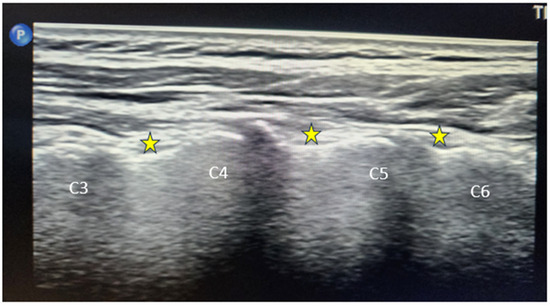

2.3.1. Ultrasound (US)-Guided MBB/RFA

Figure 1.

Long-axis ultrasound image of the cervical spine demonstrating the articular pillars at the C3–C6 levels. The cervical medial branch target points are marked with yellow stars at the waist of each articular pillar, corresponding to the typical anatomical location of the medial branches for diagnostic block or radiofrequency procedures.